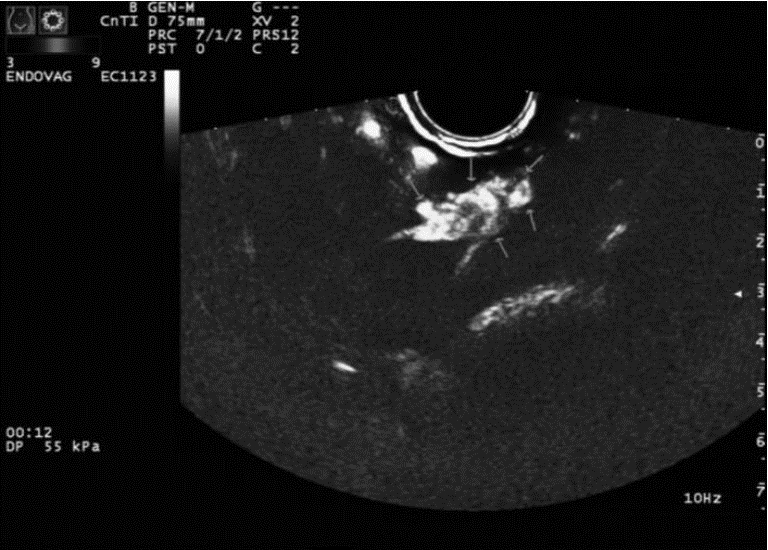

2 结果CDFI正确诊断切口妊娠和下段妊娠分别为17例、14例(图 1、图 2),CEUS正确诊断切口妊娠和下段妊娠分别为19例、20例(图 3、图 4)。CDFI、CEUS、CDFI及CEUS联合在切口妊娠与宫腔下段妊娠的鉴别诊断中差异具有统计学意义(P<0.05)。见表 1。

![]() |

| 图 2 孕囊位于子宫下段近前峡部,CDFI显示前侧壁肌层与孕囊之间的条状血流信号 |